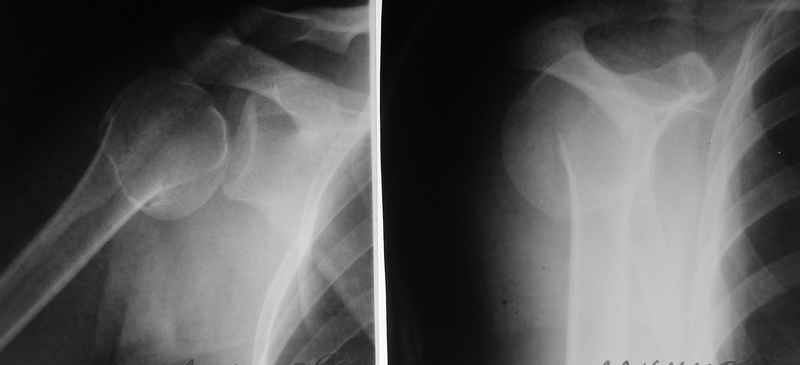

По Neer операцию рекомендовали только тогда, когда угол между диафизом и головкой составляет около 45 градусов, и переломы с меньшим углом смещения считали благоприятным для функционального результата.

Хотя "варусная импакция" в проксимальном отделе плеча срастается хорошо консервативными мерами, но в результате при восстановлении такие больные теряют часть отведения, и тем более у больной варус осложнен еще сгибанием.

Закрытые репозиции без фиксации из-за вторичного смещения неэффективны, поэтому рекомендуется репозиция с фиксацией. Методик много, кто чем владеет и отдает предпочтение закрытые-открытые, перкутанные, с блокирующими пластинами, гвоздь, множественными спицами или методом спиц по Лазареву, и осторожно с манипуляциями из=за возможности повреждения аксиллярного нерва - частый вид осложнении.

Первичное консервативное лечение рекомендуется только тем больным, когда по причинам общего состояния, например, политравма или другие тяжелые состояния больного, не позволяют оперативное лечение при первичном поступлении, тогда такие больные с самого начала предупреждаются о необходимости вальгусной или другой восстановительной операции позднее.